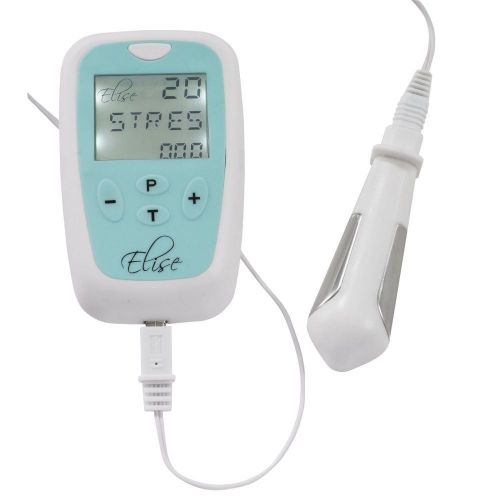

TensCare Compact Elise Pelvic Floor Exerciser For Home Use